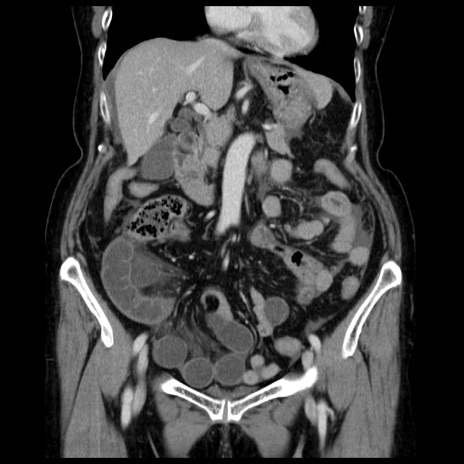

症例13(冠状断像)

【症例】70歳代女性

【主訴】腹痛、嘔吐

【現病歴】15時間程前(昨晩)より腹痛あり。今朝になっても症状の改善なく、嘔吐あり。腹痛も増悪あり、救急外来受診。

【既往歴】子宮癌全摘術後

【身体所見】意識清明、BP 121/72mmHg、P 74bpm、SpO2 100%(RA)、腹部:平坦・軟、腸雑音ほぼ聴取せず。下腹部・心窩部・臍左上に圧痛あり。反跳痛なし。

【データ】WBC 10600、CRP 0.15